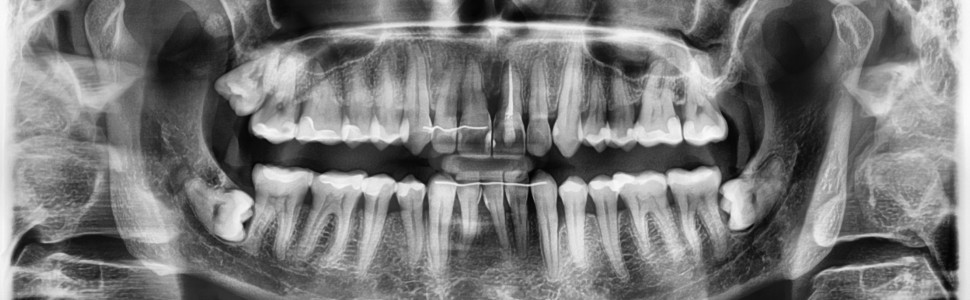

Praca opisuje przypadek rekonstrukcji periodontologicznego ubytku kości oraz brodawki międzyzębowej z wykorzystaniem ekstruzji ortodontycznej.

The paper describes a case of periodontal bone defect and interdental papilla reconstruction using orthodontic extrusion.